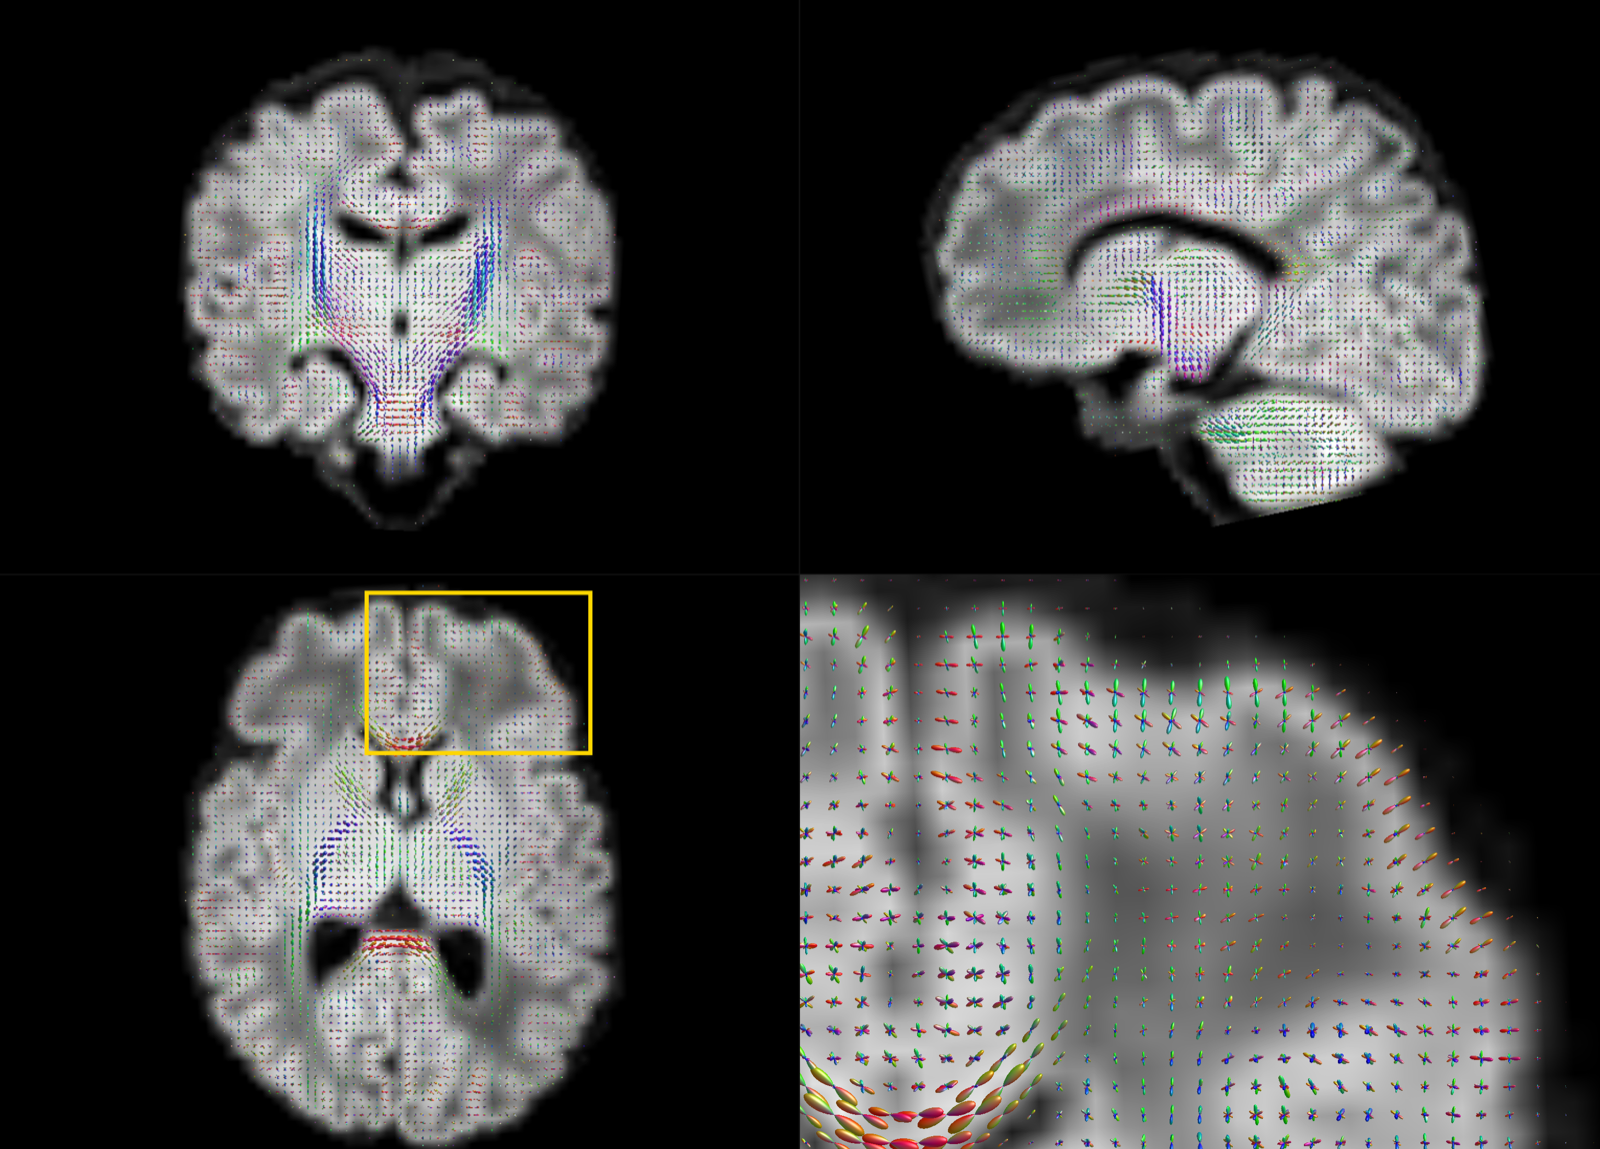

The motion-corrected super-resolved SHARD reconstructions are suitable for a wide range of analyses to explore tissue microstructure and orientation. Figure 9 displays the tissue orientation distribution function (ODF) in each voxel, derived using a group-wise 2-component multi-shell factorization. Specifically, the 5 selected subjects at term were each decomposed into a tissue component (the SH convolution of a tissue response function and ODF at ) and an isotropic () fluid component, using unsupervised convexity- and nonnegativity-constrained spherical factorization (Christiaens et al., 2017). Subsequently, the 2-component spherical deconvolution (Jeurissen et al., 2014) was repeated with the group-average response functions. The figure shows a comparison between scans at both ends of the motion spectrum. In both cases, we retrieve the major developing white matter tracts, including the corticospinal tracts and middle cerebellar peduncles shown in the figure. Figure 10 displays the tissue ODF in a preterm subject, scanned at birth (31 wPMA) and at term-equivalent age (41 wPMA). In this case, we can observe the radial tissue orientation in the developing cortex.